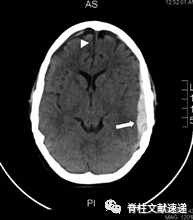

图注:55岁女性,腰椎翻修手术硬膜撕裂,术后第7天出现神经系统变化(神志错乱、失语等)。头颅CT示左侧额叶、顶叶、颞叶有硬膜下血肿,中线移位。患者被紧急送至手术室进行硬膜下血肿的清除。手术后失语症完全消失,头颅CT显示左侧血肿完全清除。